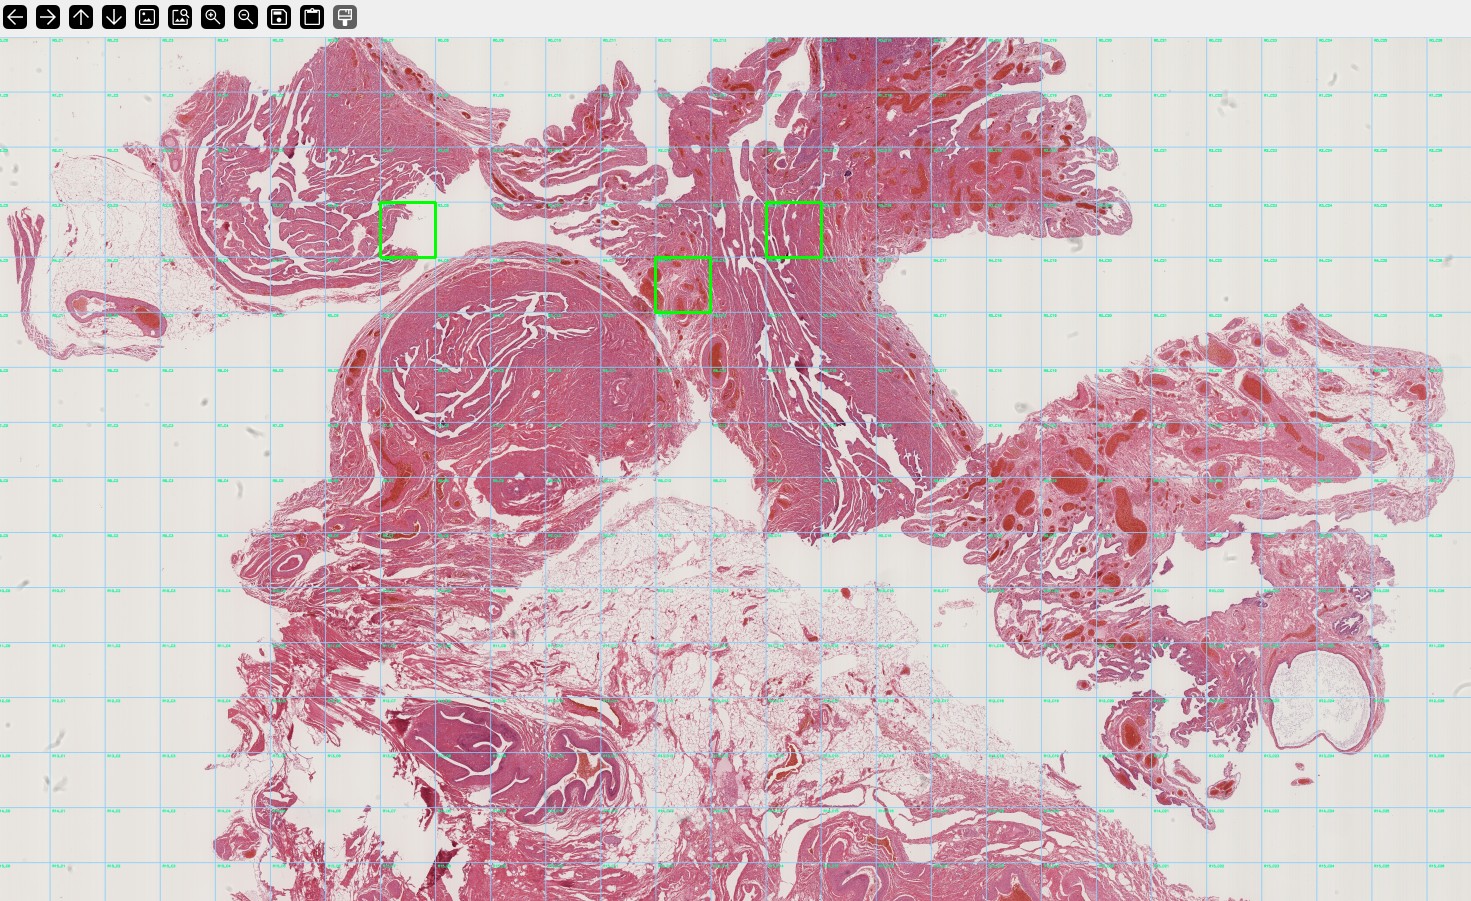

Thanks to our expertise in Artificial Intelligence, we can analyse millions of clinical data sets, MRI images or histopathological samples to detect different types of cancer

(lung, colon, pancreas, skin, etc.) at early stages, considerably increasing patients' chances of survival.